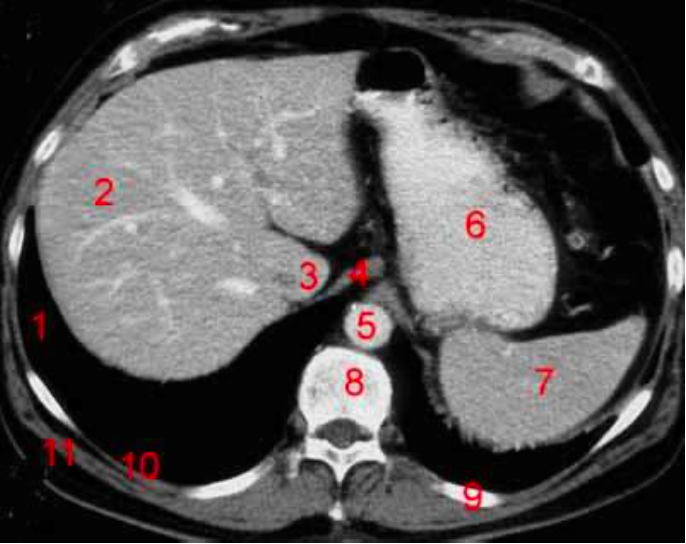

Number 3?

IVC

Number 2?

Gall bladder

Number 8?

Body of thoracic vertebra

Number 9?

Lt rib

Rt lobe of liver

Number 10?

Rt rib